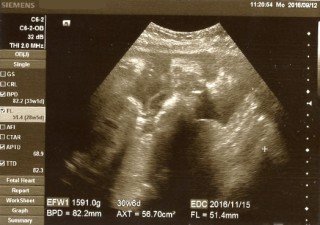

1591gと小さめの女の子です。頭は82.2mmで33w1d相当なんですが、体重は30w6d相当で、足は51.4mmで28w5d相当です。今まで小さめながらも全体的に順調に成長していたんですが、ここで足だけ成長が送れ頭だけ成長が伸びました。2週間後がどうなっているのかすごく気になります。